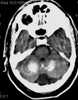

Primary familial brain calcification (PFBC), also known as familial idiopathic basal ganglia calcification (FIBGC) and Fahr's disease, is a rare, genetically dominant, inherited neurological disorder characterized by abnormal deposits of calcium in areas of the brain that control movement. Through the use of CT scans, calcifications are seen primarily in the basal ganglia and in other areas such as the cerebral cortex. [Source: Wikipedia ]